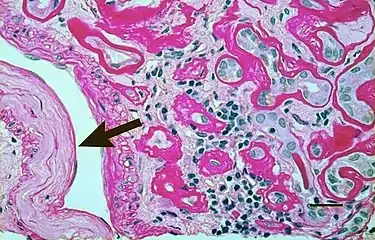

Micrograph showing renal arterial hyalinosis – pink ring right-of-centre. PAS stain. | |

In benign nephrosclerosis, the changes occurring are gradual and progressive, however, there can be sufficient kidney reserve capacity to maintain adequate kidney function for many years.[10] The large renal arteries exhibit intimal thickening, medial hypertrophy, duplication of the elastic layer. The changes in small arterioles include hyaline arteriolosclerosis (deposition of hyaline, collagenous material), which causes glomerular collapse (wrinkling and thickening of capillary basement membranes and collapse of capillary lumen) and solidification (glomeruli exhibit sclerosis and increase in mesangial matrix). The degree of scarring correlates with the degree of glomerular filtration deficit.

- Light micrograph showing signs of hypertensive nephropathy: interstitial fibrosis, tubular atrophy with thickened tubular basement membranes, and fibrous intimal thickening of a small artery (arrow).